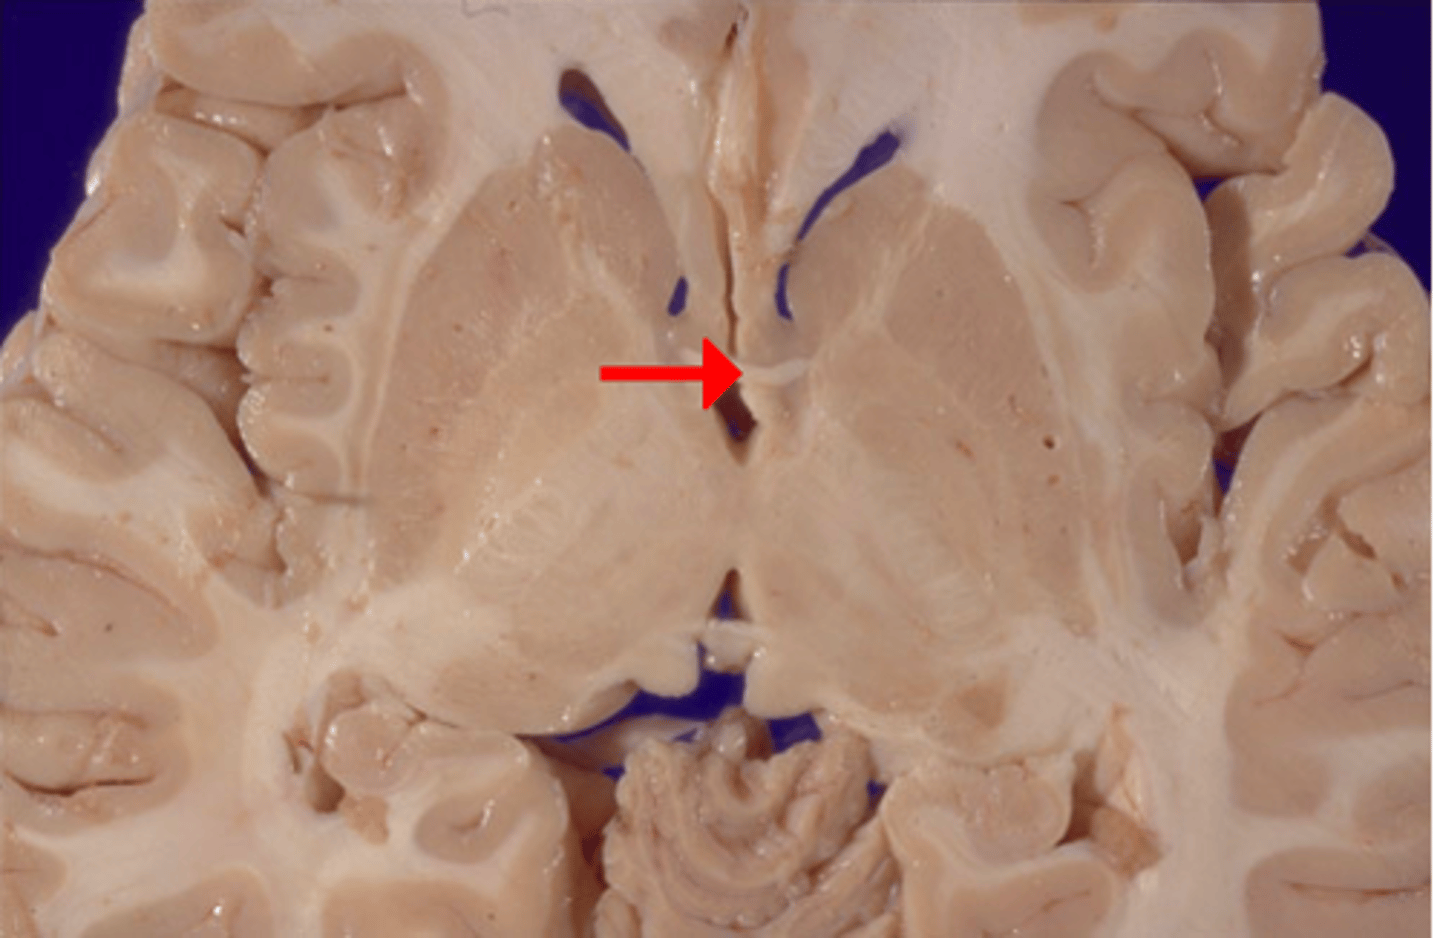

interthalamic adhesion

Connects the two thalami and passes through the third ventricle.

third ventricle

thin midline space that separates the left and right thalami.